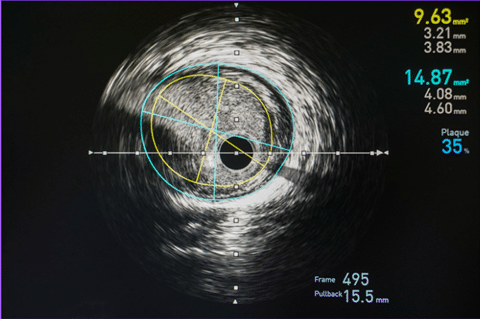

Step: 3 Quantitative Measurements:

• IVUS provides precise measurements of vessel size, plaque burden, lumen diameter, and wall thickness.

• Quantitative parameters include lumen area, vessel area, plaque area, minimal lumen diameter, and external elastic membrane (EEM) area.

Step:4 Qualitative Assessment:

• IVUS allows assessment of plaque morphology, such as calcifications, fibrous tissue, lipid pools, and thrombus.

• Plaque characterization helps determine lesion severity and guides treatment decisions.